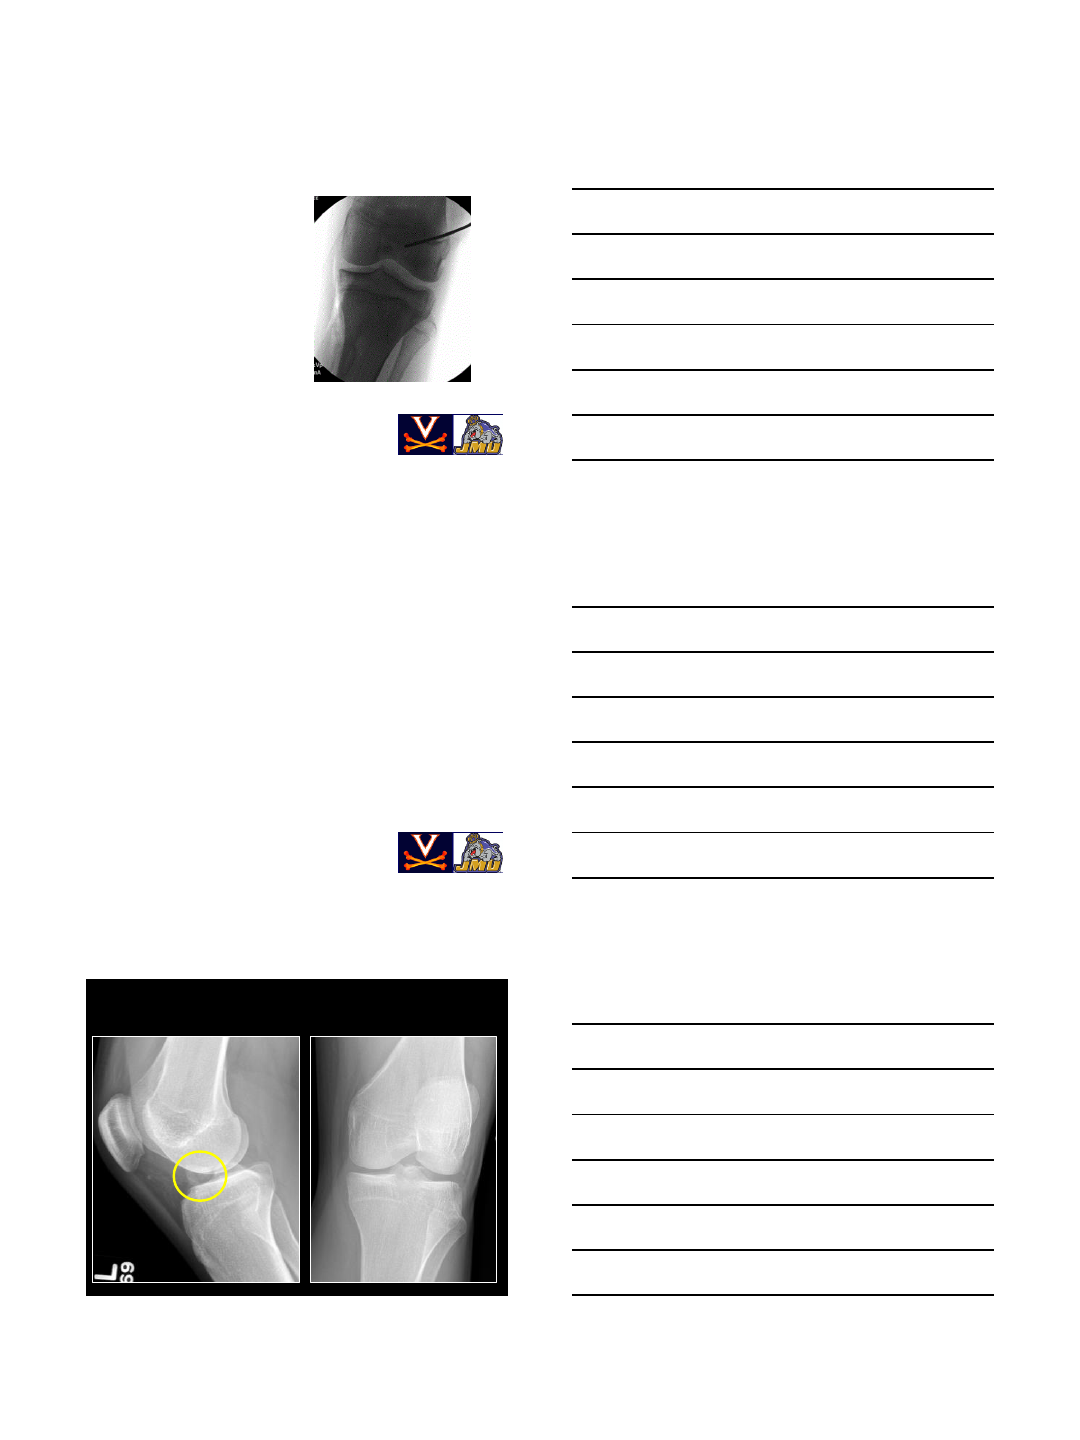

Revision ACL Case (Continued)

•On Presentation (4 months S/P bone grafting),

patient (and parents) complained of recurrent

instability and requested a second opinion

•Radiographs suggested tunnel osteolysis and

vertical femoral tunnel placement

CT

Tibial Tunnel

18mm

Femoral Tunnel